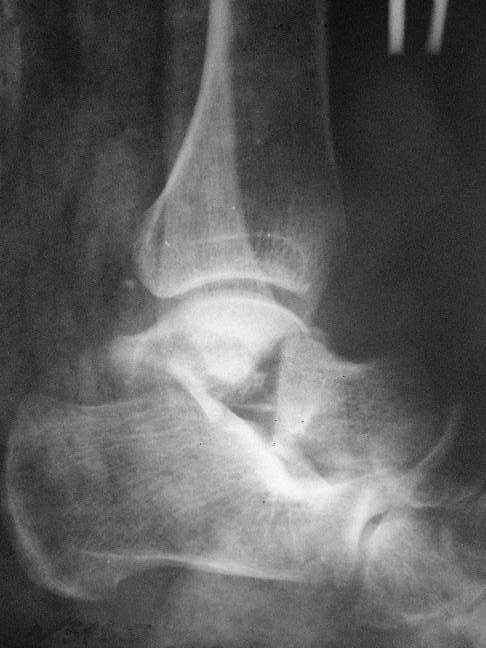

Переломовывих тарана с повреждением медиальной стороны. Через 4 часа после поступления проведена репозиция и фиксация тарана после Irrigation&Debridment. Частичное несращение медиальной лодыжки не беспокоит, вернулся к активному образу жизни. Полная нагрузка разрешена через 11 недель. Финальные снимки через 11 месяцев.